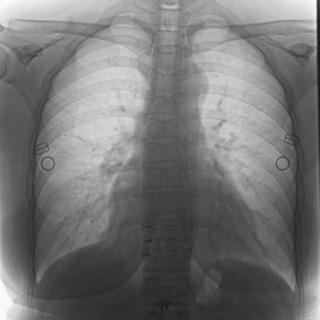

不同于常規(guī)DR只能進(jìn)行平片攝影檢查,普利德多功能動(dòng)態(tài)平板DRF動(dòng)靜兼?zhèn)?,可?shí)現(xiàn)大幅面低劑量透視檢查,在日常的體檢工作中,比如胸部及肺部檢查,可對重疊部位病變進(jìn)行可視化觀察及多角度旋轉(zhuǎn)體位,發(fā)現(xiàn)疑似病灶可瞬時(shí)完成高清點(diǎn)片,顯著提高診斷的準(zhǔn)確性。

動(dòng)態(tài)采集幀率最高可達(dá)30幀/s,影像細(xì)膩流暢,便于醫(yī)生對細(xì)微病變的觀察。17×17英寸大幅面成像,在透視過程中能對患者的胸部腹部等部位實(shí)現(xiàn)大范圍覆蓋,便于從整體上觀察組織信息,更加全面且精準(zhǔn)的捕捉病灶。